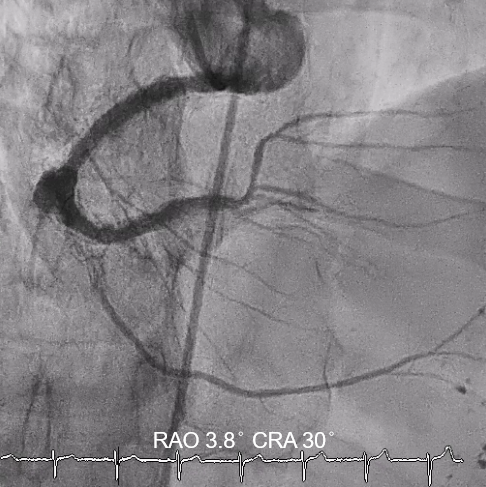

Subsequent coronary angiography identified a pseudoaneurysm in the right coronary artery (RCA), without any evidence of extravasation.

In this coronary catheterization procedure, a guidewire was used to cross the lesion and advanced to the posterolateral branch (PL). An intravascular ultrasound (IVUS) examination was conducted, revealing a pseudoaneurysm in the mid-right coronary artery (m-RCA). To cover the pseudoaneurysm, a 3.5 x 16 mm cover stent was deployed in the m-RCA at a pressure of 16-18 atmospheres for 15-20 seconds, repeated twice. Subsequently, the cover stent was further post-dilated with a 3.75 x 15 mm non-compliance balloon at 18-20 atmospheres for 10 seconds, also performed twice. Optical coherence tomography (OCT) was then performed, showing a post-dilation stent MSA of 7.40 mm² with good apposition and expansion. The cover stent was additionally dilated with a 4.0 x 30 mm drug-eluting balloon (DEB) at 6 atmospheres for 60 seconds. The final angiography demonstrated TIMI grade 3 flow without any extravasation.

Case Summary

Post-intervention angiography demonstrated improved blood flow in the affected artery. The RCA pseudoaneurysm was effectively sealed, and subsequent imaging confirmed appropriate stent placement. The use of IVUS and OCT allowed for optimal sizing and placement, leading to a successful outcome.